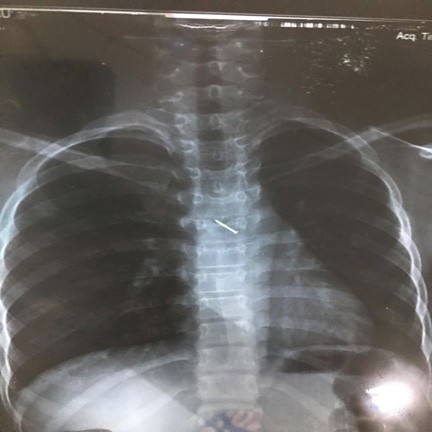

Hình ảnh đinh ghim trong lồng ngực bệnh nhân qua chụp X- quang. |

Tại đây, bệnh nhi được chụp X- quang, bác sĩ xác định trong lồng ngực bé có dị vật hình đinh ghim đã chuyển bệnh nhân đến Bệnh viện Nhi Trung ương để theo dõi và tiếp tục điều trị.

Tại Bệnh viện Nhi Trung ương, các bác sĩ chẩn đoán có dị vật là một chiếc đinh ghim dài khoảng 1,5cm nằm ở vị trí thành ngực của bé gái. Các bác sĩ đã hội chẩn và quyết định phẫu thuật nội soi lấy dị vật ra khỏi lồng ngực của bé.